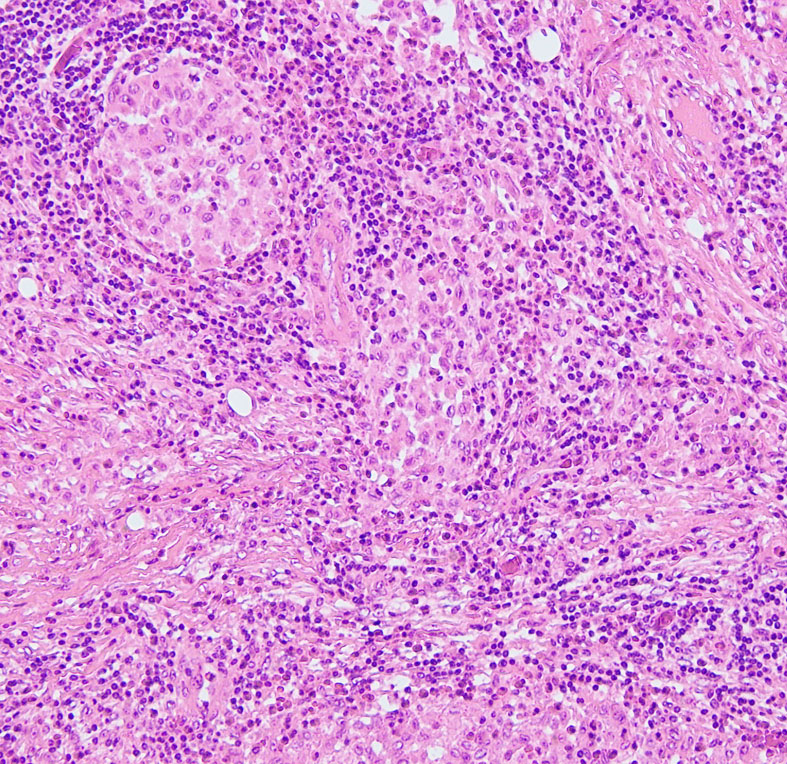

LCHの病理像

頭蓋骨のLCHの病理像です。左はHE染色,右はランゲルハンス細胞に特異性の高いCD1a(specific to dendric Langerhans cells) 染色です。多数のLangerhans cellとともに,組織球,リンパ球,好酸球,多核細胞など多彩な細胞浸潤があります。これは活動性のLCHの病巣から摘出したものです。

自然緩解して収まった病巣を生検術で摘出しても,このような典型的な病理像がなくて慢性炎症像がみられるだけのことがあります。その場合は確定診断がつきません。

左は,活動性の病巣です。右は,活動期が終わり慢性炎症所見を伴いながら肉芽種に移行する過程です。